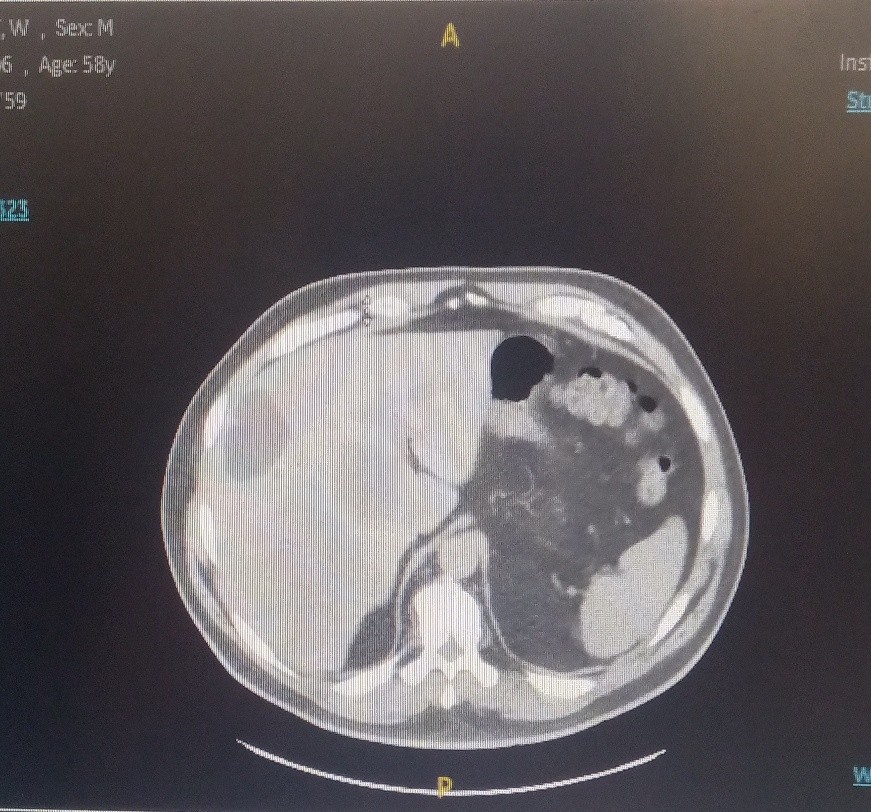

The patient is a 59-year-old male who was accidentally found to have liver lesions when he underwent (CTA) computed tomography angiography for chest pain (Figure 1). A subsequent positron emission tomography scan (PET) revealed metastatic disease in the liver (Figure 2), most likely originating from the primary sigmoid colon cancer (Figure 3). CT-guided liver biopsy of the liver lesion confirmed metastatic disease with histologic features consistent with a primary of colorectal origin. His blood test showed elevated colonic embryogenic antigen (CEA) of 38 ng/ml.

Figure 1. CTA of the chest showing multiple liver metastasis

Figure 1